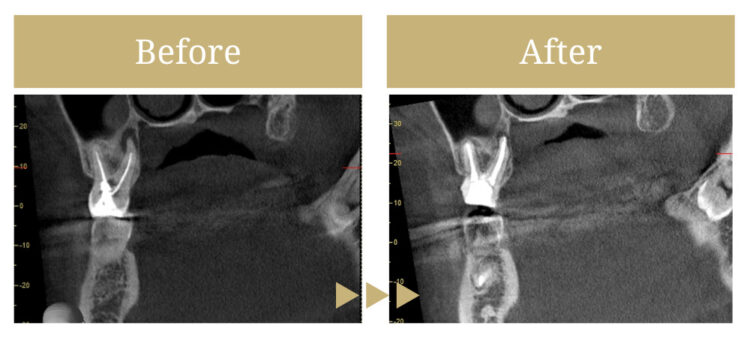

CTを撮影したところ、根管治療が不十分な部分があり、歯の根の先端に細菌の膿が確認される状態でした。再度の根管治療が必要な状態でしたので顕微鏡を用いた精密根管治療を提案させていただきました。

治療前の状態

根管治療の際の薬剤が十分に入りきっていないところがあり、再度の感染が進みつつある状態でした。

治療後の状態

歯の根の先端まで消毒が行われ、薬剤も先端まで入っています。治療の効果もあり、根の先端の膿も縮小してきています。